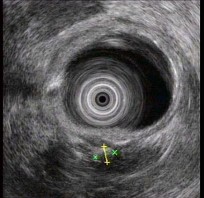

(单选题)胰腺超声内镜如图,最可能的诊断是()。

A:胆管结石

B:急性胰腺炎

C:胰腺癌

D:慢性胰腺炎

E:胰腺囊腺癌